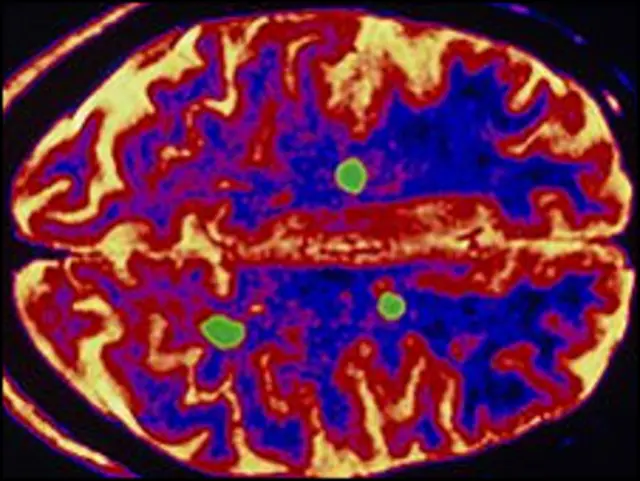

اس مرض میں جسم کا دفاعی نظام دماغ میں موجود خلیوں اور مائلین نامی مادے کو نقصان پہچانا شروع کر دیتا ہے جس کے نتیجے میں دماغ اور جسم کے دیگر حصوں کے درمیان پیغام رسانی کا نظام متاثر ہو جاتا ہے۔